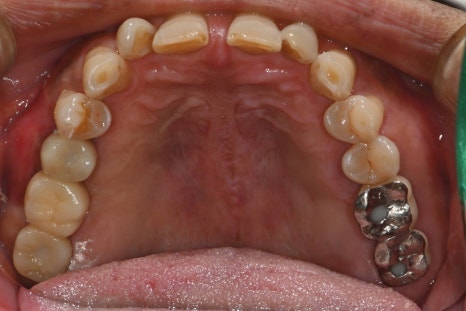

Left photo: panoramic X-ray taken after the final prosthetic restoration was placed.

Right photo: intraoral photo after treatment was completed.

The prosthesis was made with zirconia material, resulting in a strong yet aesthetically pleasing finish with excellent harmony with the natural teeth.